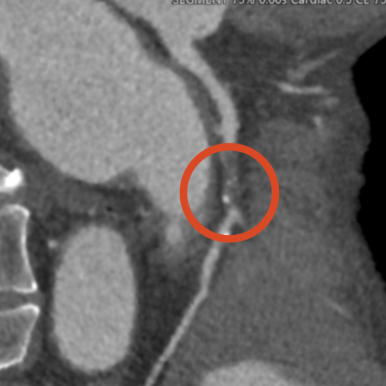

심전도, 24시간 심전도(홀터), 심장초음파, 관상동맥 CT 등 심장 질환을 진단하는 검사는 표준화된 장비와 정밀한 해석이 동시에 필요합니다. 특히 심장초음파와 CT는 숙련된 전문의가 판독해야 정확도가 높습니다.

순환기내과 전문의는 수천 건 이상의 심장 관련 판독과 치료 경험을 기반으로 심장 질환의 초기 징후를 빠르고 정확하게 포착할 수 있습니다. 특히 협착이 미세하거나 증상이 애매한 경우, 경험 있는 전문의의 판단이 진단을 좌우합니다.

관상동맥 CT